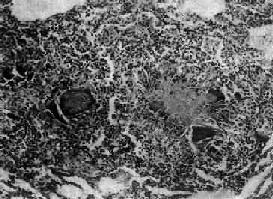

结核结节(tubercle)是在细胞免疫基础上形成的,由类上皮细胞(epithelioid cell)、Langhans巨细胞加上外围局部集聚的淋巴细胞和少量反应性增生的纤维母细胞构成。当有较强的变态反应发生时,结核结节中便出现干酪样坏死。巨噬细胞体积增大逐渐转变为类上皮细胞,呈梭形或多角形,胞浆丰富,染淡伊红色,境界不清。核呈圆或卵圆形,染色质甚少,甚至可呈空泡状,核内可有1~2个核仁。多数类上皮细胞互相融合乃形成Langhans巨细胞,为一种多核巨细胞,体积很大,直径可达300μm,胞浆丰富,核与类上皮细胞核的形态大致相同,核数由十几个到几十个不等,有超过百个者。核排列在胞浆的周围呈花环状、马蹄形或密集在胞体的一端(图18-1)。

结核性肉芽肿

图18-1 结核性肉芽肿

结节中央为干酪样坏死,周围绕有类上皮细胞、Langhans巨细胞以及淋巴细胞等